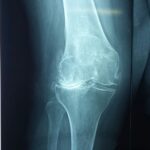

Total knee replacement surgery is commonly indicated for severe osteoarthritis of the knee. Osteoarthritis is the most common form of knee arthritis in which the joint cartilage gradually wears away. It often affects older people.

In a normal joint, articular cartilage allows for smooth movement within the joint, whereas in an arthritic knee the cartilage itself becomes thinner or completely absent. In addition, the bones become thicker around the edges of the joint and may form bony “spurs”. All of these factors can cause pain and restricted range of motion in the joint.

Your doctor will diagnose osteoarthritis based on the medical history, physical examination, and X-rays.

X-rays typically show a narrowing of the joint space in the arthritic knee.